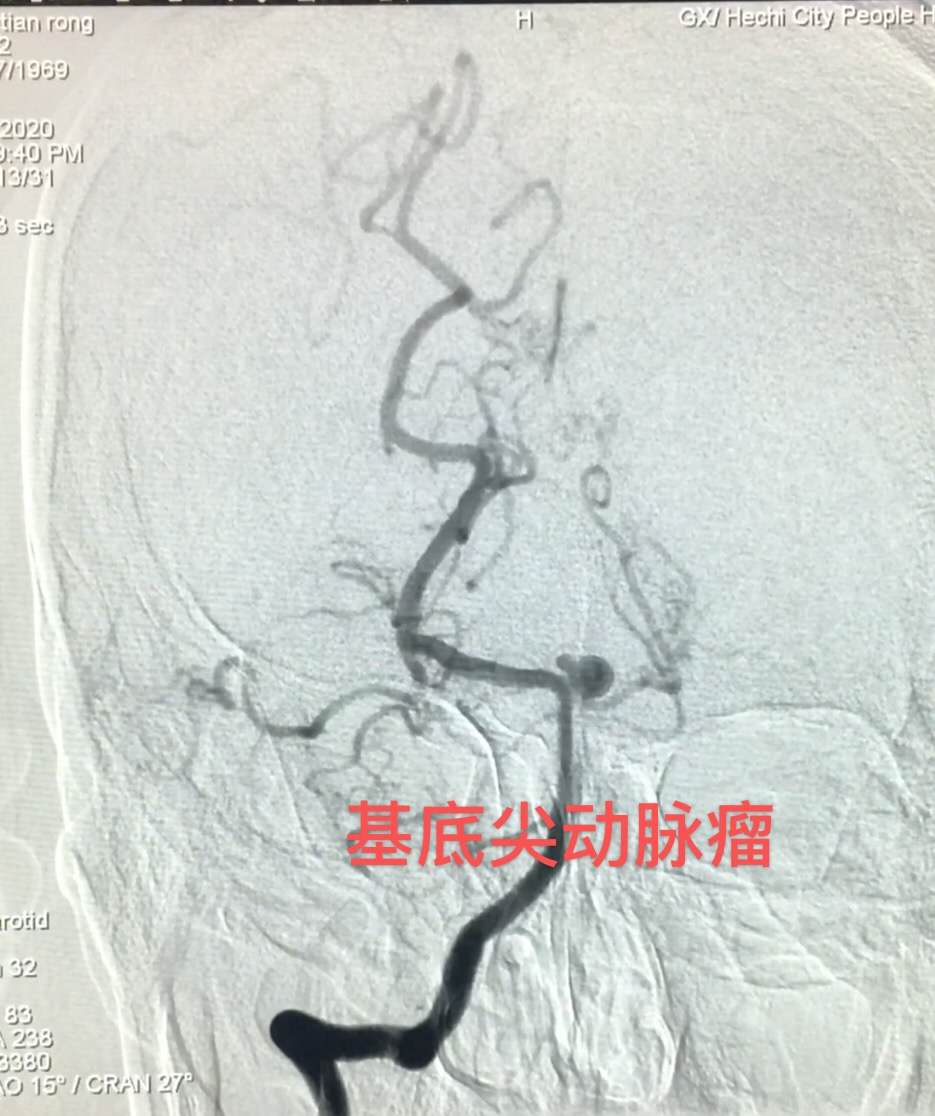

据了解,51岁的候先生因“突发意识障碍”被工友送至我院急诊科,急诊CT提示蛛网膜下腔出血,收治神经外科后立刻进行CTA检查,确诊为基底动脉顶端动脉瘤破裂出血。这是一种致残率和死亡率很高的病变,如果不及时处理,随时都有可能发生病情恶化甚至死亡。神经外科医疗团队当即组织制定详细的手术治疗方案,在与家属充分沟通后,在最短的时间内为侯叔叔进行了全脑血管造影术、底动脉顶端动脉瘤电解脱弹簧圈介入栓塞术。术中造影显示侯叔叔的颅底出现云状异常,可见基底动脉顶端一大小约6.5mm×5.8mm×2.8mm的囊性动脉瘤,且伴有“烟雾病”。手术医生要在变形变细、形似云雾缭绕、错综交织的血管内找到动脉瘤并摘除,手术难度非常大……最终经过3个半小时的努力,手术顺利完成。术后,在经过4次腰椎穿刺术等后续相关辅助治疗后,患者恢复清醒,并无神经系统相关并发症,终于转危为安,现已康复出院。

基底尖动脉瘤